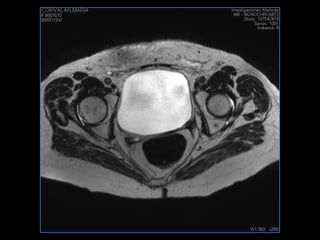

PROTOCOLO pelvis SAG T2, Y FAT SAT (FINOS) AXIAL T1  AX FAT SAT CON   GADOLINIO :  AX T1 Y COR T1 SAT: NO  FASE: RL THK: 3MM  COIL:  GAP: (FACTOR 1.4) 1MM FOV: 40 CM NEX:2 SINCRONIZACION RESPIRATORIA EN 3 O 4 CICLOS ALE